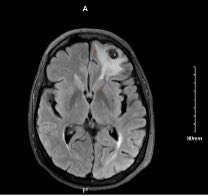

Neuroautopsy from a pt with disseminated coccidiomycosis. Prominent leptomeningeal inflammation with focal breakthrough into underlying parenchyma = meningoencephalitis. Beautiful yet scary spherules filled with endospores are clearly visible on H&E/LFB. #neuropath #forensicpath